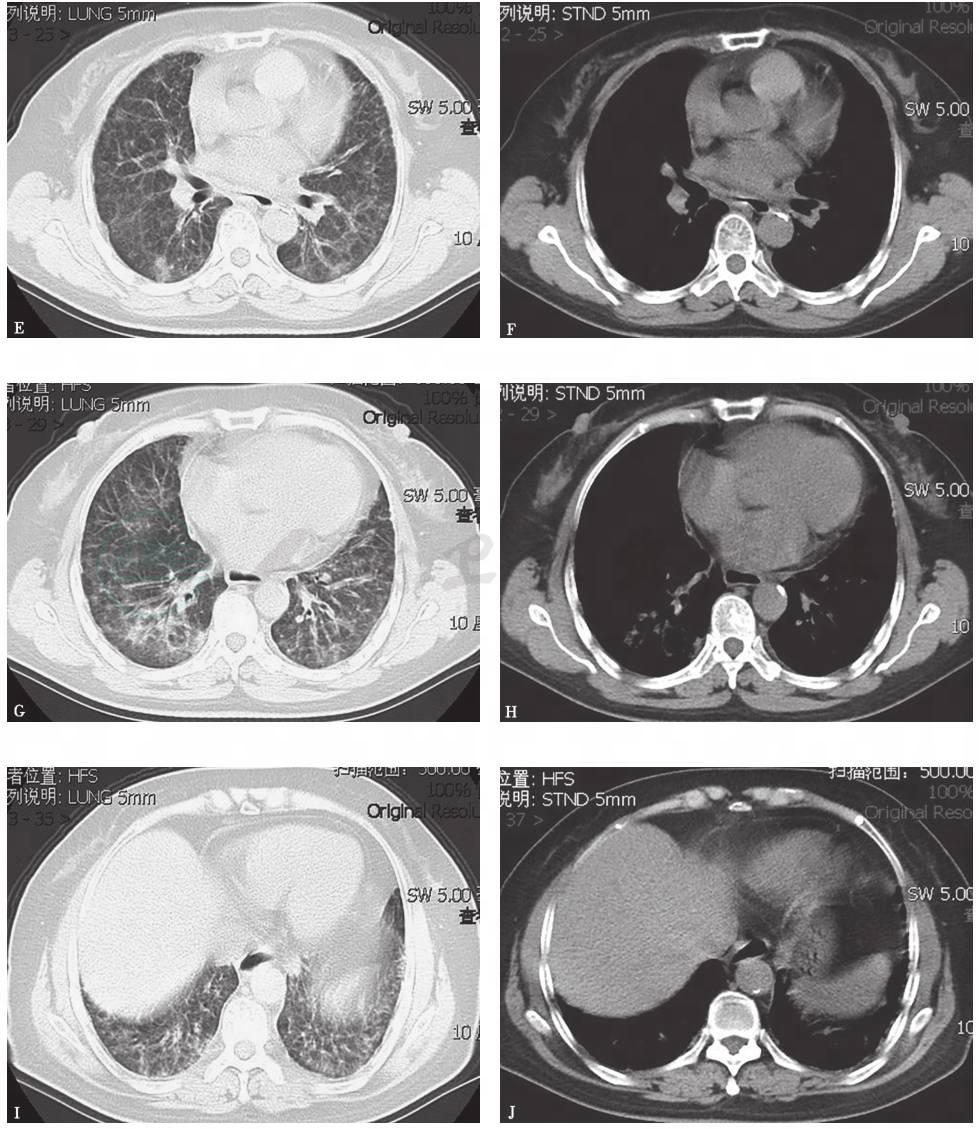

胸部CT:双肺弥漫间质性病变伴多发小结节(图1)。2个月后,随着病程延长,原有结节样病灶增多,病灶融合,形成磨玻璃及实变影,并出现双侧胸腔积液和少量心包积液(图2)。

图1 胸部CT表现(2014-03-05)

图2 胸部CT表现(2014-05-22)

4.胸部影像学表现由双肺弥漫性磨玻璃影并多发小结节样改变,逐渐进展至大片磨玻璃影、局部实变结节并双侧胸腔积液。

胸部X线检查可见双肺弥漫高密度影,双侧少量胸腔积液(图4),1个月后病灶进一步增多、加重(图5)。胸部CT显示病灶进一步融合增多,伴双侧胸腔积液和心包积液(图6)。

图6 胸部CT表现(2015-06-03)

胸部CT可见双肺多发斑片影、结节影,双侧少量胸腔积液,少许心包积液